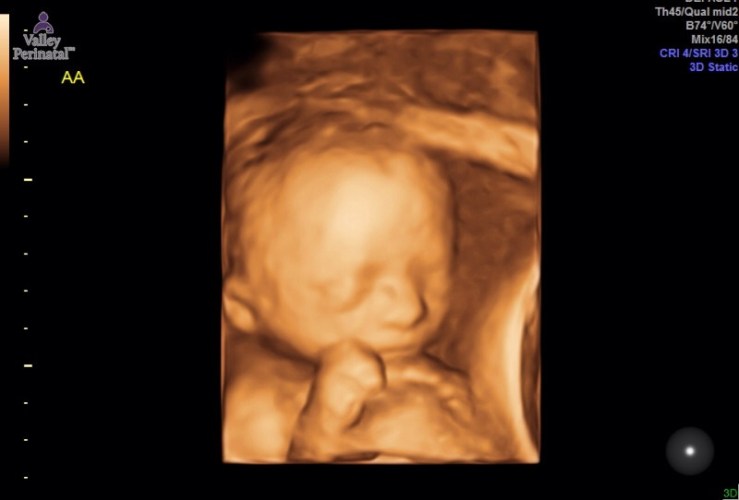

Here’s the two best pictures from the ultrasound. Of course baby B would not sit still so his picture is a little blurry but I promise you he is perfection! Luke thinks baby A looks like a Prudence while baby B looks like a Leonard and I’m just relieved they look like babies!!

After I was done being violated, while my husband watched no less, we got to see the boys! And OMF-ingG they look completely different at 22.5 weeks than they did at 19.5. Not gonna lie, at 19.5 weeks they were a little creepy looking – all skin and bones, no chubby cheeks or distinguishing features. Now they look like little boys with fat cheeks and little button noses. I may actually have a couple little chunkers on my hands as they both measured almost a week ahead in their growth and weight! I love fat babies. Like there is nothing cuter than a baby who’s fat rolls spill over themselves but I would prefer to not have to birth fat babies – you know just get healthy while you’re in me and then blossom into the cutest chunk ever  when you get to the outside world, be nice to your mom’s insides please!